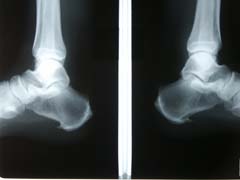

足の痛みにも踵骨棘、足底腱膜炎、種子骨障害、アキレス腱炎、アキレス周囲炎、有痛性外脛骨、モートン病、足根管症候群、外反母趾などたくさんのものがあります。その中でも日常でみられるのは踵骨棘・足底腱膜炎です。

また、レントゲンを撮ってみると踵の骨のところに棘のようなものがありそれが原因で痛みがでている時があります。

朝に痛みが出やすい。歩行痛、足底にしびれ、踵の底が腫れたり、肥厚して硬くなってきたりします。

踵や足裏に症状が出るときは足底やふくらはぎの筋肉がうまく使えてなかったりして固くなり緊張をおこしてしまうことがあります。また足底の筋肉はふくらはぎ→太もも(裏)→腰・背中・首・頭と筋膜で繋がっているため、身体の後面のどこかの場所の緊張によって引っ張られて起きるケースもあります。また足首の関節が繰り返す衝撃によって機能しなくなってでることもあります。